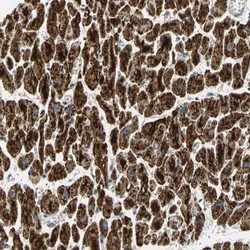

Immunohistochemistry

NBP1-85607 IHC